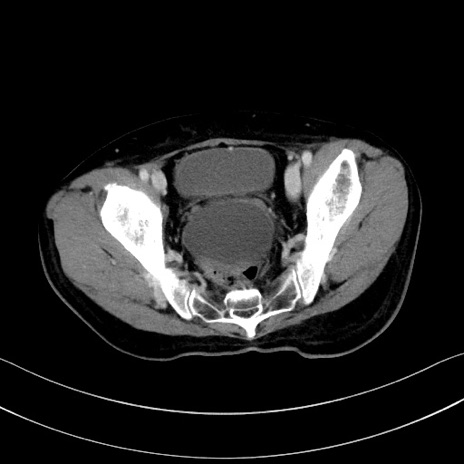

症例28(横断像)

【症例】60歳代男性

【主訴】嘔吐

【現病歴】胃癌にて胃全摘後。食思不振が悪化し、夜中に嘔吐することがある。

【既往歴】胃癌、胃全摘、脾摘、胆摘後

【データ】WBC 5900、CRP 10.56